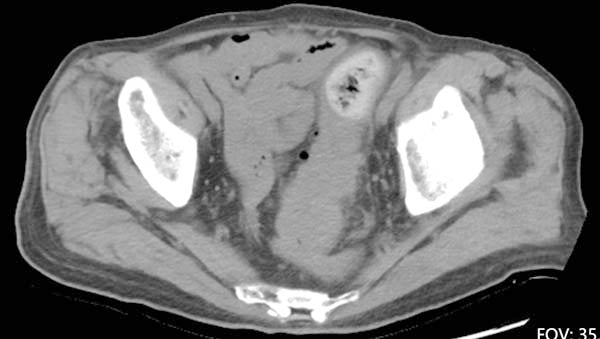

Beijing Chaoyang Hospital admitted a 93-year-old patient with locally advanced rectal cancer.

Navigating a bulky tumor and a restricted pelvic space, the surgical team executed a precise Total Mesorectal Excision (TME).